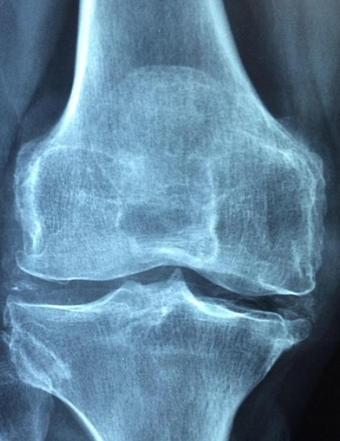

가장 잘 알려진 원인은 노화입니다. 나이가 들면 관절을 덮고 있는 연골이 점차 마모되고 손상됩니다. 연골은 충격을 흡수하는 완충 역할을 하는데, 이 기능이 약해지면 뼈와 뼈가 직접 맞닿아 통증과 염증을 유발합니다. 이로 인해 중·장년층에서 무릎, 고관절, 손가락 관절염이 흔히 발생합니다.